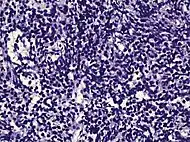

| Small-cell carcinoma | 0.3–2%[14][15][notes 1] | ![]() |

Half of cases have usual acinar components[1] |